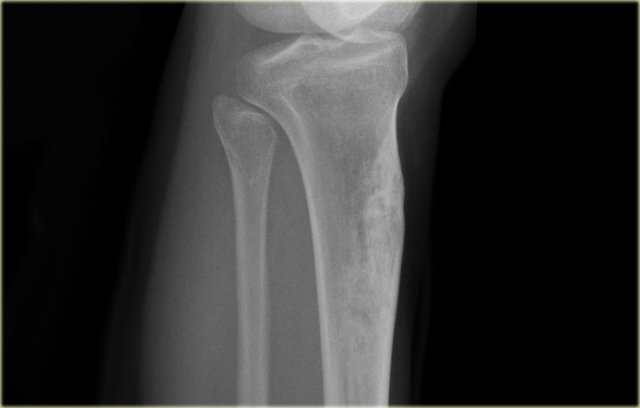

The image shows a calcified lesion in the proximal tibia without suspicious features.

This could very well be an enchondroma.

There were other features that favored the diagnosis of a low-grade chondrosarcoma like a positive bone scan and endosteal scalloping of the cortical bone on an MRI (not shown).

A chondrosarcoma was diagnosed at biopsy.